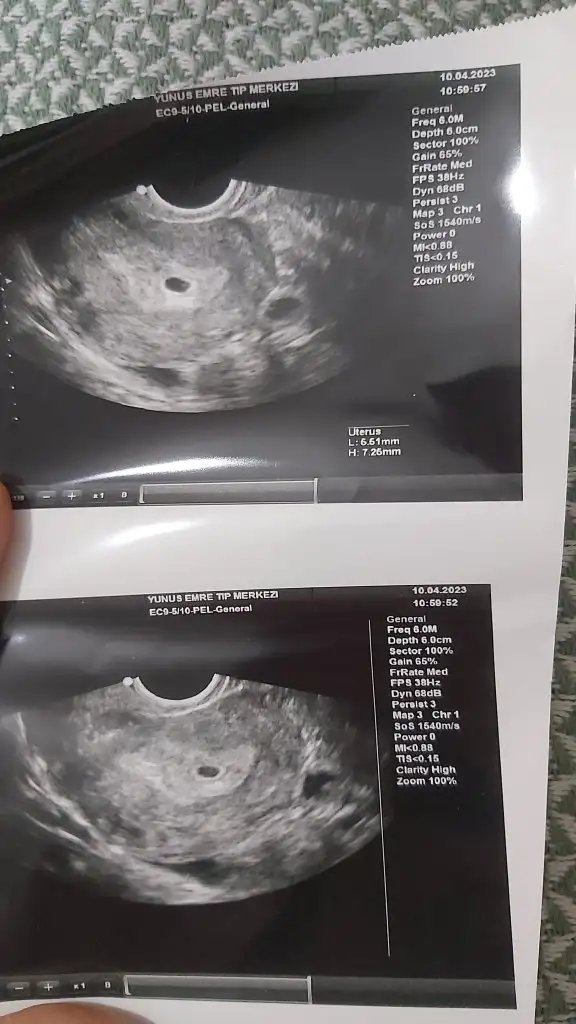

Geç döllenmedir canım senin beta nasıl ilerledi bugün verdin mi?Kızlaaar doktora gittik yeni çıktık sayılır ultrasonda üç haftalık falan gözüküyor kese net görülmedi birşey var ama kan da olabilir dedi doktor.. Aklıma takılan şey neden hesaba göre beşken ultrasonda üç hafta gözüküyor sizce

İlk defa ve ilk kontrol yarın tahlil sonuçlarını atacağım duruma göre pazartesi yada salı günü tekrar gel bakalım yine dedi benim ilk gebelik on yıl önceydi çoğu şeyi hatırlamıyorum bileİlk defa mı gittiniz bu doktora? Öyle diyorsa en azından bir açıklama yapabilirdi yani. Benimde öyle 7 haftalık gözükmesi gerekiyordu ilk gebelikte ama büyümedi. Yani çok değişiyor veya doktorda bir sıkıntı var bilemiyorum..

Merhaba alttan mi muayene ettiBunu gördü ama kan pıhtısı da olabilir dedi rahim kalın dedi bir tane yumurtalık kisti var dedi atılamayan yumurta kisti olur ya ondan hani önemsiz

O zaman normal görememesi hatta yine iyi görmüş o küçük keseyi bende bir kaç gün önce gittiğimde hesabıma göre 4+6 dim karından hiç birsey göremedi hatta bir panik oldu alttan bakti hemen sonra güneş gibi doğdu kesem günümeMerhaba Hayır karından muayene etti

Makineler de fark ediyor bunu fark ettim, çoğu kişinin alttan görmüş doktorlar, benim de 4+6 randevum vardı kese için karından gördüO zaman normal görememesi hatta yine iyi görmüş o küçük keseyi bende bir kaç gün önce gittiğimde hesabıma göre 4+6 dim karından hiç birsey göremedi hatta bir panik oldu alttan bakti hemen sonra güneş gibi doğdu kesem günüme